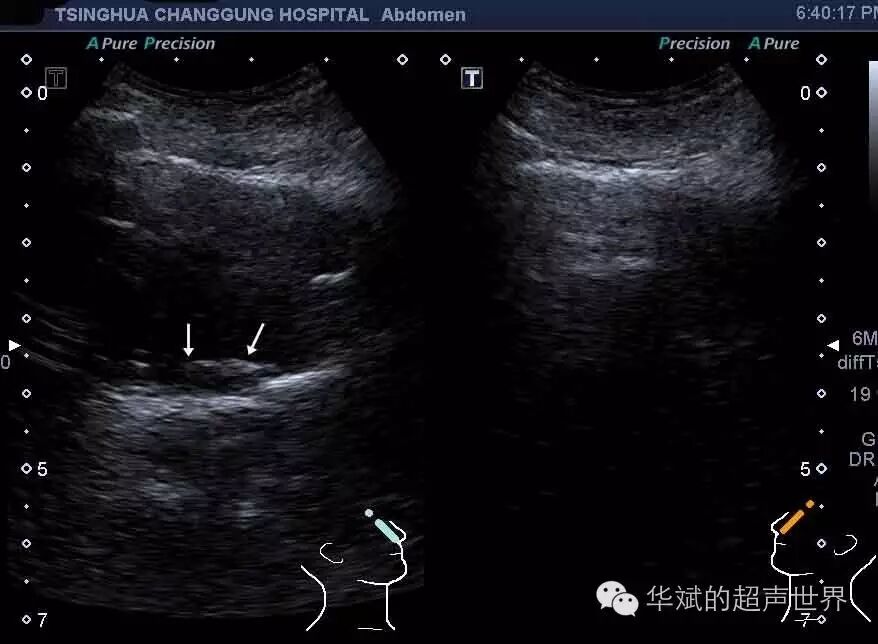

典型病例2  患者男,31岁,上感一周,鼻塞,流涕,超声示右侧上颌窦积液和增生的粘膜组织。

图5 急性上颌窦炎。右图为正常的左侧上颌窦声像图,窦腔内结构不能显示。左图为右侧上颌窦内积液,并可显示增生的粘膜结构(箭头)。